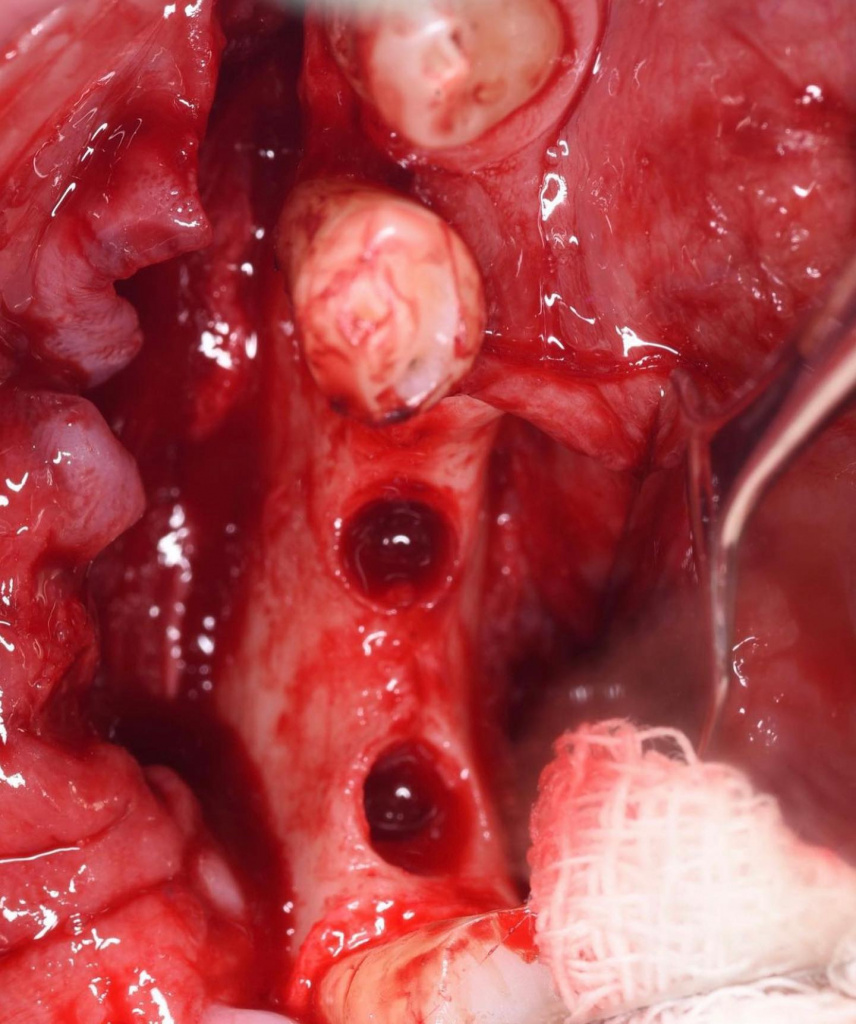

- Удаление имплантатов AlphaBio

- Забор блоков для костной пластики с косой линии нижней челюсти